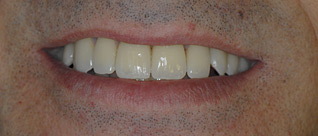

Je veux supprimer les bridges et retrouver un beau sourire.

Au final toutes les dents sont individualisées et les manquantes remplacées par des implants.